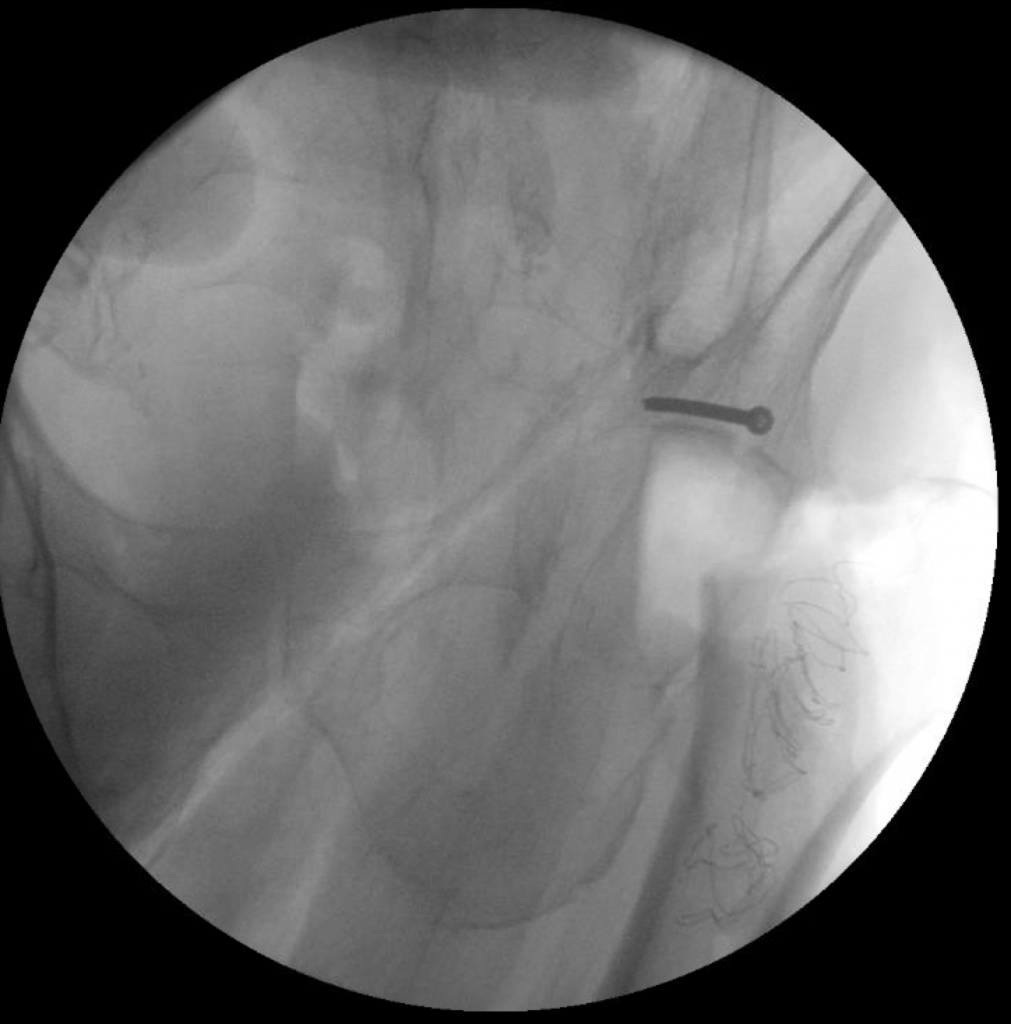

The patient underwent simultaneous acetabular ORIF and complex THA reconstruction by Dr. Darwin Chen and Dr. David Forsh (Chief of Orthopaedic Trauma). A Kocher-Langenbeck approach was used for exposure. The anterior and posterior columns were secured together using a single posterior-to-anterior screw just superior to the acetabulum. An acetabular shell was implanted with excellent inherent stability, followed by screw fixation into the superior dome as well as inferiorly into the ischium.